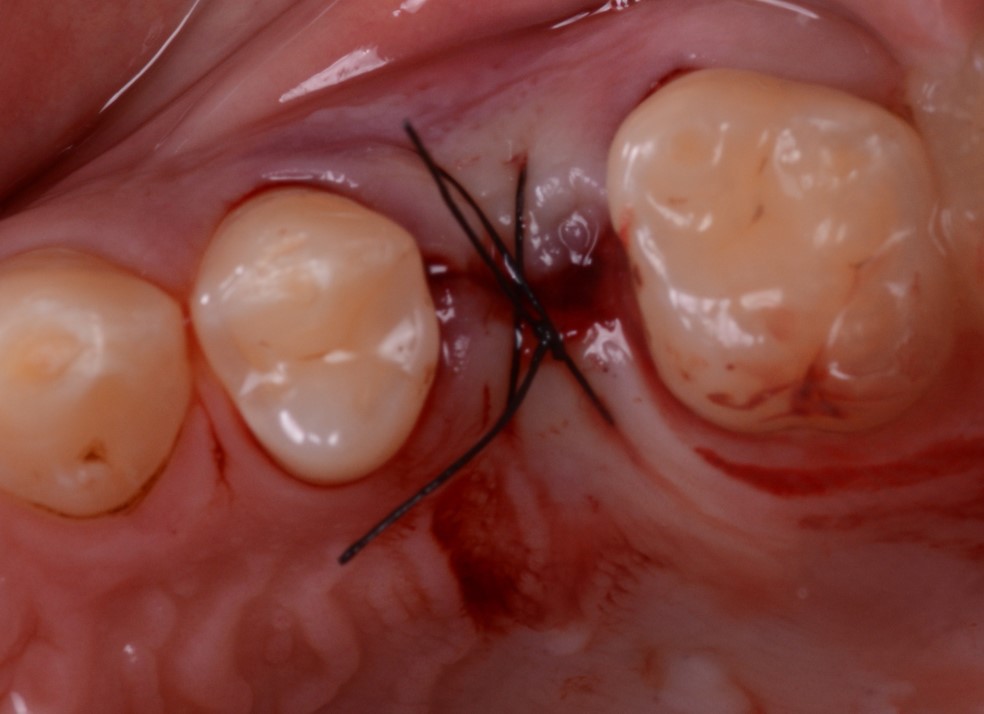

Presentiamo un caso di riabilitazione di edentulia singola attraverso una corona supportata da impianto prodotto con moderna tecnologia di laser sintering. Il paziente, maschio di 45 anni senza particolari problemi di salute generale, con una buona salute orale, fumatore ma non bruxista, si presentava alla nostra attenzione per la risoluzione di un problema di edentulia singola a carico dell’elemento #25 (secondo premolare superiore di sinistra) (Fig. 1,2).

Fig. 2. Situazione pre-operatoria, visione occlusale. Il secondo premolare di sinistra (#25) è stato da poco estratto perché non più recuperabile e il paziente.

L’impianto prescelto era stampato in 3D (Type K®, AndrewMedical, Carate Brianza, Monza, Italia) con stampante stereolitografica (RenAM 500Q®, Renishaw, Wottonunder-edge, Gloucestershire, UK) e pertanto caratterizzato da una superficie altamente porosa (Fig. 3), in grado di promuovere l’osteointegrazione. Il posizionamento dell’impianto avveniva dopo somministrazione di anestetico locale per infiltrazione, sollevamento di lembo mucoperiosteo a spessore totale, e preparazione del sito con kit implantare dedicato. Inserito l’impianto (Fig. 4), si procedeva a suturare i lembi (Fig. 5).

guarigione sommersa

Fig. 5. Si optava per una guarigione sommersa.